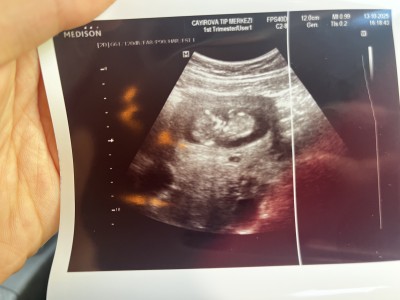

İlk fotoda mı öyle hissettin 2. De mi bende ilkte kız ikincide erkeğe benzettim amin inşallah

Yok yapısından baktim daha narin kafası vucuduyla eşit gibi . İkincide de zaten bacak arası görünmüyor ki